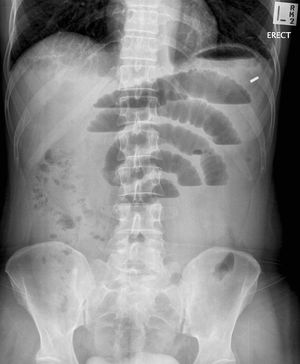

Intestinal obstruction

different height of air fluid level in the same loop of small intestine